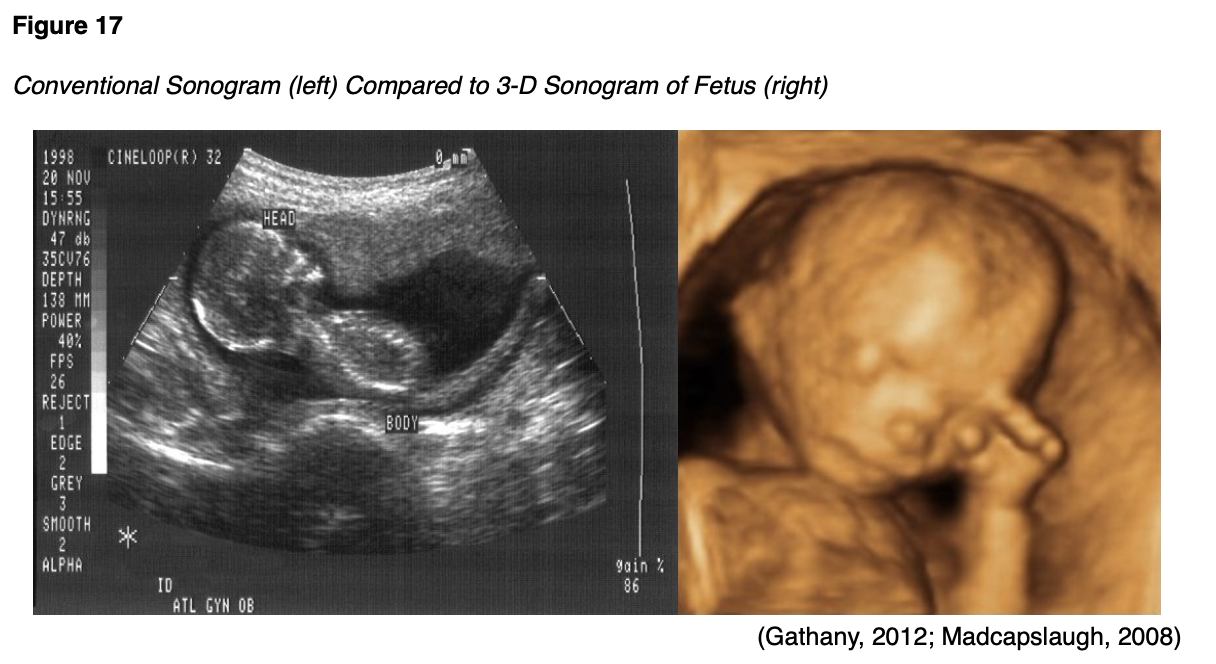

Ultrasound